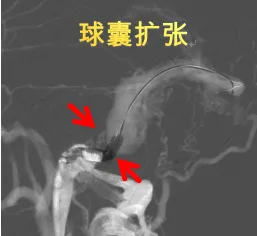

术前CT提示:双侧髋关节脱位,股骨近端畸形,股骨颈、股骨头短小,真臼未发育

术后复查骨盆正位片:髋关节假体位置良好,粗隆下截骨处愈合良好